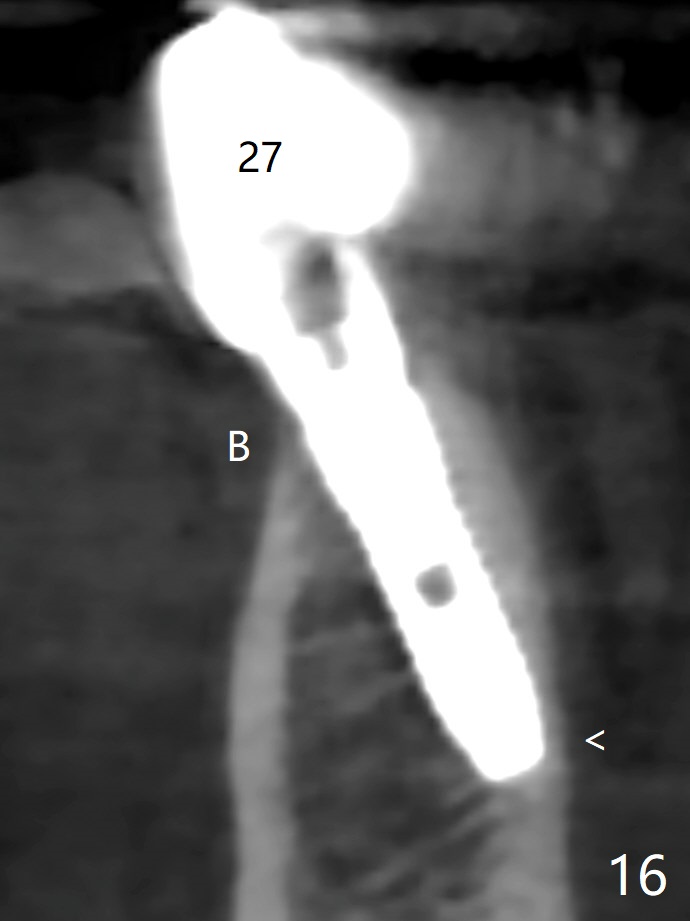

The mesial defect at #27 appears to have been repaired 8 months postop (Fig.8,9 *); there is no bone loss at 1-piece implant sites. The gingival recession seems to remain the same before and after removal of the provisional FPD (Fig.10,11). The bulging abutment at the cervix is less prominent when a straight abutment is used and prepared (Fig.12, 4.5x5.5(5) mm). There is no bone loss at #23, 25 and 27 sites 2.5 years post cementation (Fig.12-15), although the trajectory of the implants could be improved by using surgical guide (Fig.16-18).